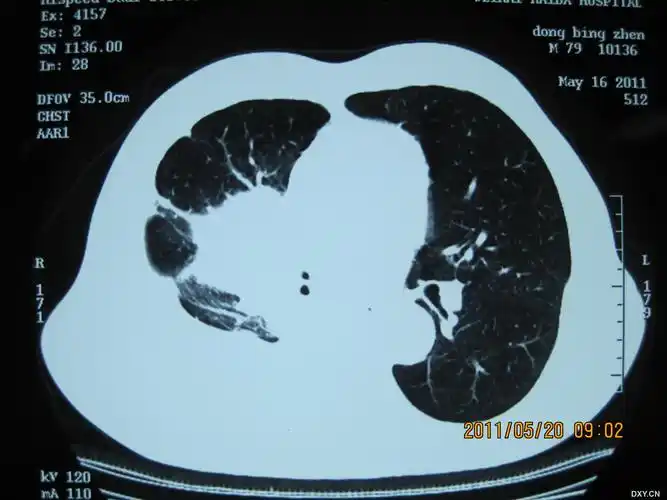

中央型肺癌ct

简述中央型肺癌特点及影像表现

在ct上,肺癌按照发生部位可以分为以下3种类型: 1,中央型肺癌:指肿瘤

中央型肺癌肺内多发转移一例!

影像基础知识:中央型肺癌ct表现及报告书写!

右肺中央型肺癌

中央型肺癌一例!

中央型肺癌一例直接征象和间接征象都有哪些